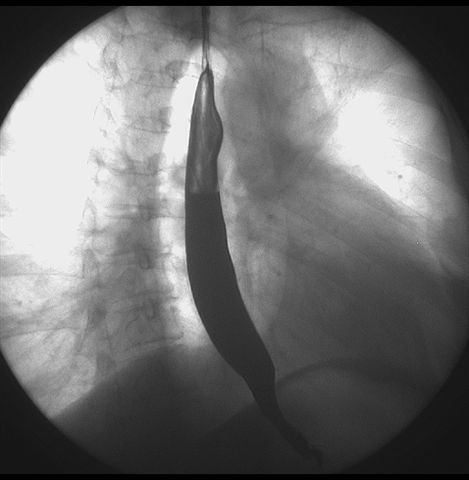

标题: X6872:F,69y,胃部不适。

胃窦至幽门段胃壁僵硬,扩张受限,局部纠集粘破坏,呈杵状。提示溃疡癌变可能性大。

胃窦癌可能性大,建议胃镜活检。钡剂太稀,吃的有点多。

支持考虑胃窦癌可能,胃内滞留液太多,胃窦部僵硬。

瀑布型胃,胃粘膜那是一个乱,窦部充盈不好,第16幅窦部粘膜反倒又很顺,先定个胃炎胃窦炎胃窦癌待排之类,建议进一步作胃镜检查。

胃窦部见钡池影,局部粘膜紊乱,纠集呈杵状改变,胃壁扩张受限,胃窦癌可能性大,建议胃镜检查.

胃窦部管腔扩张度较差,形态略有改变,胃窦粘膜显示欠佳,胃窦部占位可能性大,结合胃镜活检。

胃窦部狭窄、稍僵硬,考虑胃窦癌?建议胃镜检查。

北京肿瘤医院胃镜诊断皮革胃。